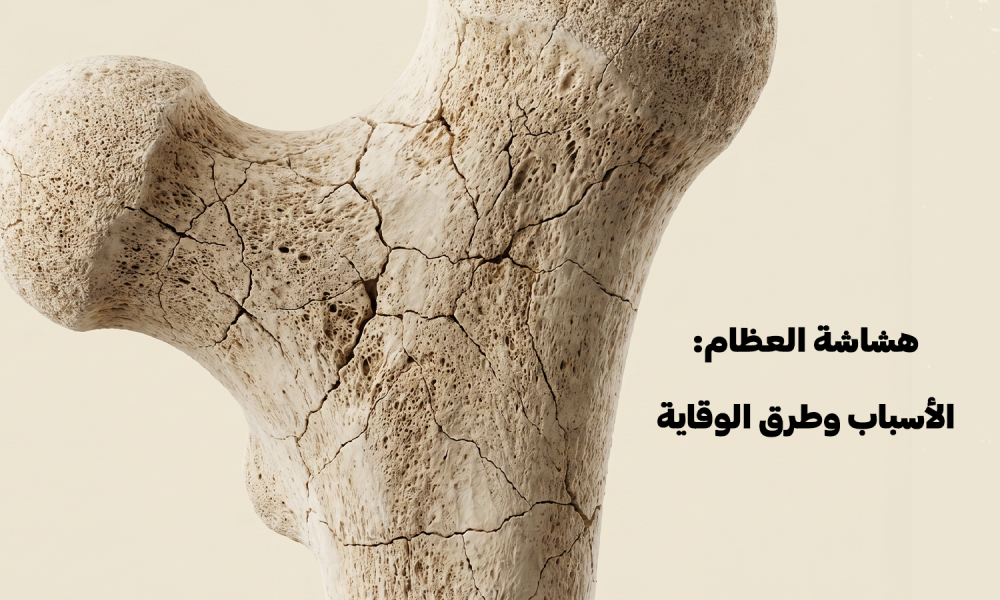

تعرف على طرق الوقاية من هشاشة العظام وتقوية العظام لتقليل خطر الكسور والحفاظ على النشاط اليومي.